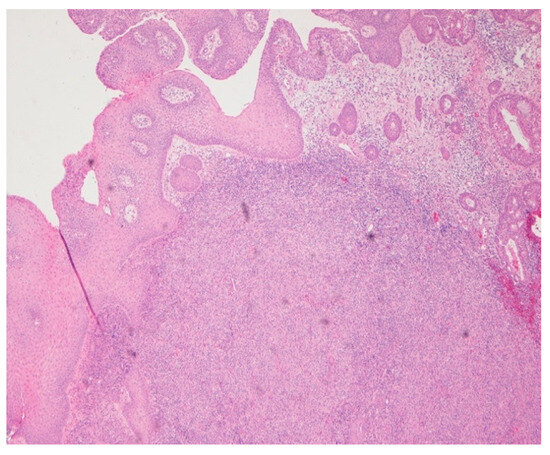

Intraoperatively, the nasal mucosa appeared friable, and the cartilaginous septum was fragmented and necrotic. Tissue samples were collected for histological examination. Histopathological evaluation of the biopsied cartilage and mucosa revealed squamous epithelial hyperplasia and surface erosion with associated crusting. The lamina propria was markedly expanded and infiltrated by a dense, diffuse inflammatory infiltrate consisting of lymphocytes, histiocytes, plasma cells, and occasional multinucleated giant cells. Notably, numerous intracellular amastigotes, consistent with Leishmania spp., were identified within histiocytes (Figure 2 and Figure 3). These findings were highly suggestive of mucosal leishmaniasis in the context of chronic nasal inflammation. Laboratory tests revealed normal blood counts and renal function, with minimal inflammatory marker elevation. Serologic testing was positive for rK39, supporting a diagnosis of active Leishmania infection, although PCR testing was negative, and CPA was indeterminate.

Figure 2. Hematoxylin and eosin (HE) 4×. Chronic inflammatory infiltration, with dense diffuse lymphohistioplasmocytic infiltrates.